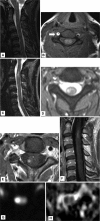

Results: Four women and one man with a median age of 52 years (range, 31-75 years) were admitted. Three patients had anterior spinal artery infarction and two patients had transverse infarctions. All patients underwent spinal MRI within 24 hours; the findings were normal in four of the five patients. After 1-2 days, T2-weighted MRI generally exhibited focal cord enlargement and hyperintensity in all patients, while spinal-cord enhancement appeared after 2-11 days.

Conclusions: Acute spinal-cord ischemia may have a typical course on MRI. MRI findings are usually normal in the acute phase, but spinal cord swelling and T2 abnormality are expected after several days, while gadolinium enhancement appears even later after symptom onset. The sensitivity and specificity of MRI can be increased by repeated MRI in patients suspected of acute spinal-cord ischemia.